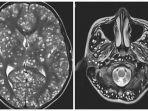

Ratusan Cacing Pita Memakan Otak Remaja Ini, Diduga Ia Gemar Konsumsi Daging Babi Setengah Matang

Memang tak dapat dipungkiri, sebagian orang (yang tak dilarang baik secara agama atau medis) gemar menyantap daging babi.